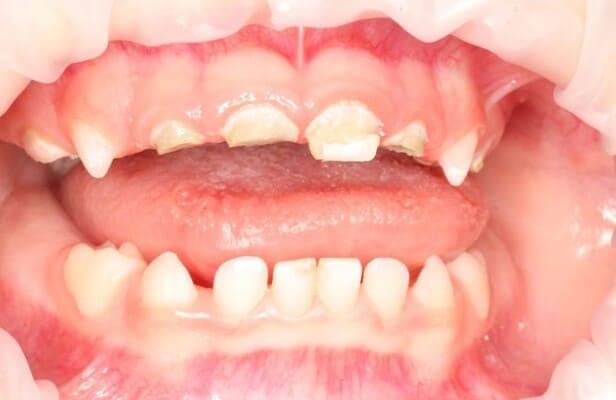

Один рік і два місяці вік дитини. Хтось скаже: «Що там тим зубам можна лікувати?!» Однак є ситуації, коли каріозний процес розвивається просто блискавично. Часто це пов’язано з порушеннями у формуванні твердих тканин ще внутрішньоутробно. А коли такі зубчики прорізуються, руйнування відбувається просто «на очах». Вісім із восьми зубів уражені, а 4 з них потребують часткового видалення пульпи («нерва»). На цьому етапі зуби вже починають турбувати і не зважаючи на юний вік дитини, зволікати не можна. Завдяки високій компетенції наших анестезіологів, які працюють з дітьми від самого народження і навіть з передчасно народженими, ми можемо проводити відповідне лікування в анестезіологічному забезпеченні за потреби навіть з першого зуба. Верхнім зубчикам, які сильно уражені, служити до 7-8 років, тому вони покриваються стандартними естетичними цирконієвими коронками, які дають максимальний результат по надійності, функції та естетиці. Година з половиною роботи і дитина може знову кусати без болю і дискомфорту. Важливо пам’ятати: для лікування зубів ніколи не буває “зарано”, це потрібно робити тоді, коли є відповідні показання